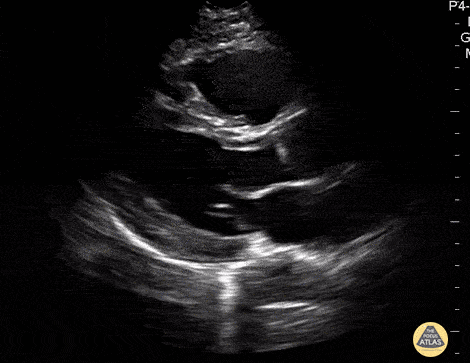

Normal Cardiac Anatomy - Parasternal Long Axis - Normal

In this view we see the muscular left ventricle and the smaller left atrium separated by the mitral valve near the bottom of the screen. The aortic outflow tract (valve and root) comes off the left ventricle superficial to the left atrium. The most superficial chamber seen in this view is the right ventricle, separated from the left ventricle by the interventricular septum. The heart is surrounded by the bright hyperechoic pericardium. At the very bottom of the screen, the round structure outside the pericardium is the descending thoracic aorta in transverse view. Hannah Kopinski - MS4, Dr. Lindsay Davis - NYU/Bellevue Department of Emergency Ultrasound, Dr. Matthew Riscinti - Kings County Emergency Medicine